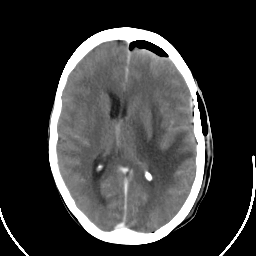

Metastatic bronchogenic carcinoma: Roentgen-ray CT (post-op) -- Slice #12

[Home][Help][Clinical] Slice 12